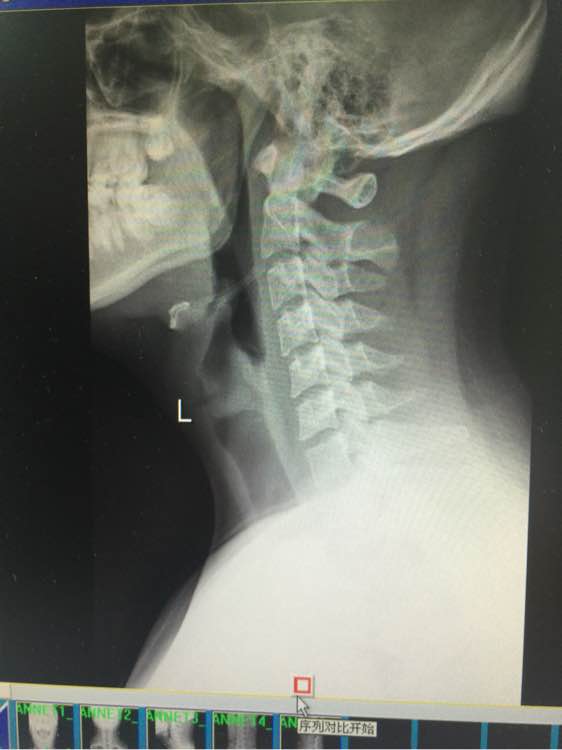

谁能帮我看看寰枢椎关节半脱位,供血不足

站不稳,坐不稳,走不稳, 做什么都飘飘的,走路不平衡,躺着还有塌陷的感觉 除了早上醒来 舒服点,越到下午越来越严重, 感觉无时无刻人就像在船上 左右摇晃的 偶尔更换体位 耳朵鼓鼓的 (这是国庆最严重时候 现在还是晕,没那么晕了,但还是没好 以下一直影响生活到现在)尿尿要扶墙,洗澡不敢洗太久 靠着墙,刷不了牙,刷牙晃动脑袋也更晕,有时候晚上坐着就犯晕,血压高,145 95以上 躺着血压就正常,

可是龙氏做了以后更严重了,我才不敢去的啊!我的片子严重吗?

你的症状也不严重呀 就是枢椎跟大椎的事 有点轻微的退行性变 压迫硬膜囊 病状不应该出现你说的那么严重 你这个正骨复位改变一下压痛点就好了

卖阳光的少年

你的意思是指 片子 反应出来的不严重,只不过是症状重 就好比同样是牙痛 有的痛睡不着觉 有的人痛发低烧 有的人一点感觉都没有